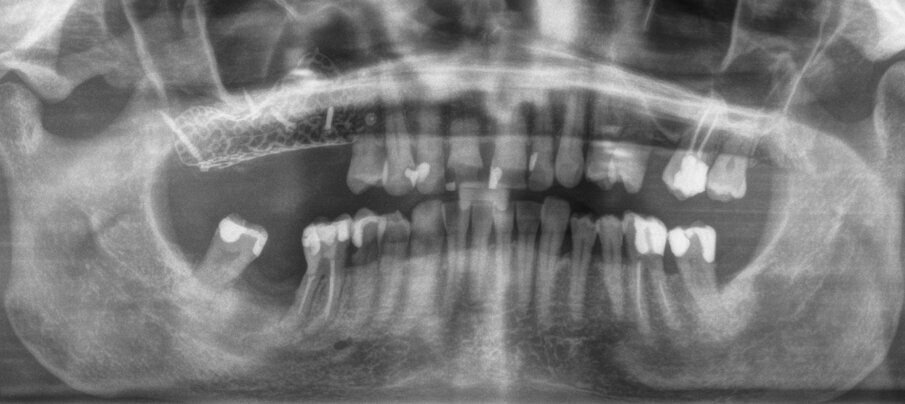

Una paziente di 62 anni, ASA I, non fumatrice e non diabetica, con malattia parodontale precedentemente trattata, si è presentata per una riabilitazione implanto-protesica del mascellare superiore (Fig. 1). L’analisi radiografica, eseguita tramite ortopantomografia (OPT) e tomografia computerizzata cone-beam (CBCT), ha rilevato la presenza di un difetto osseo verticale nel primo sestante, dovuto alla completa perdita del processo alveolare (Figg. 2, 3). Dopo aver discusso con la paziente le possibilità di trattamento, è stato accettato il trattamento proposto come prima scelta, ovvero la ricostruzione ossea del processo alveolare e la successiva riabilitazione mediante corone singole su impianti.

Dopo 14 giorni, sono state rimosse le suture, sono stati raccolti dati relativi al decorso post-operatorio, è stata verificata l’assenza di deiscenze o esposizione o infezione della griglia, ed è stata eseguita una radiografia OPT (Fig. 22). La paziente ha riferito un livello medio di dolore pari a 0, su una scala VAS da 0 a 10, con una media di 1,6 FANS assunti al giorno, durante le prime 2 settimane; inoltre, la paziente ha riferito gonfiore significativo, un piccolo livido esterno sul volto, e la difficoltà ad aprire la bocca. Secondo il questionario Postoperative Symptom Severity (POSSe), si è registrato un valore di 32, indicativo di un moderato disagio postoperatorio.